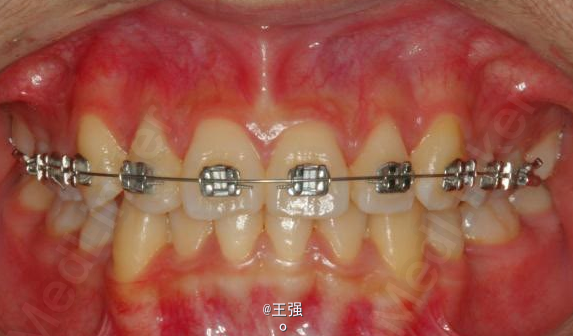

在临床上,我们常常会遇到亚类病例,对于亚类病例,有时需要不对称拔牙,常见的不对称拔牙方法有:上颌对称,下颌数目对称但是位置不对称。还有上颌对称,但是下颌数目不对称。其目的就是为了取得尽可能理想的尖窝对应咬合关系 该病例右侧是中性关系,左侧是中性偏远中关系,上颌中线正,下颌中线左偏约1mm。左侧磨牙关系距离中性关系约差2mm左右。如果采用对称性拔除下颌左右四,我们面临的问题是,一、如何保证矫治后上下中线一致,二、如何保证左侧磨牙关系矫治后为中性关系。治疗过程中势必会用到不对称牵引。我个人认为除非是功能性的因素,矫治过程中最好不要用不对称牵引。 关于中线和磨牙关系的问题,我认为应在矫治计划制定时就应考虑到,而不是等到矫治第三阶段所谓精细调整阶段再来解决。事实上到了这个阶段采用了不对称的牵引,即使暂时取得了中线对齐的矫治目的也是不稳定的。 这个病例,用了不对称的拔牙,右下拔四,左下拔五。下颌牙齿在漂移的过程中(几乎没有外来力量),下前牙自然就会向右比向左多漂移一些,中线在下颌还没有开始矫治时就对齐了,左下六因没有五的存在,自然就向近中多漂移一些,和上颌六形成中性关系。接下来的矫治就会非常简单,而结果自然也非常稳定。